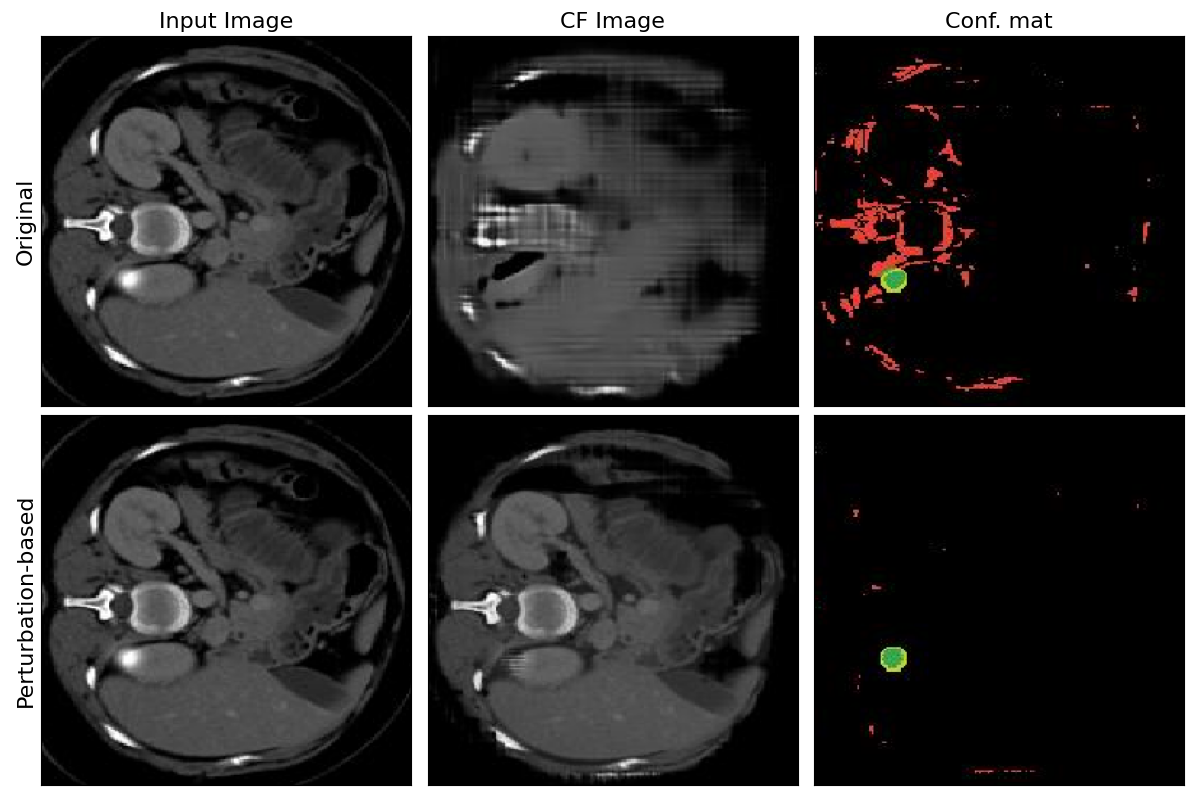

7.3 Original vs Perturbation-based generator

Refer to caption

Figure 4: Examples of images generated with original and perturbation-based Singla et al.* pipelines.

Within this experiment, the counterfactual explainer of Singla et al. is taken to validate the significant improvement employing the perturbation-based generation in terms of FID and IoU scores. The perturbation-based image generation generates much higher fidelity images. Instead of reconstructing the whole input image from scratch, the decoder learns to output only the changes needed to flip classifier decision. Figure 4 gives qualitative evaluation of the generated images following the two approaches.